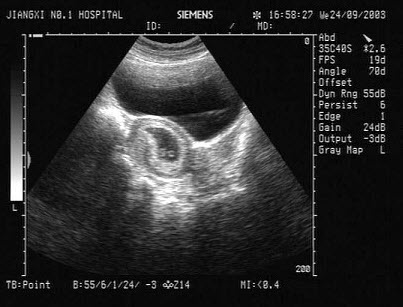

23、单项选择题

患者男46岁,既往有胆囊结石病史,上腹部疼痛不适年余,加重1个月,皮肤、巩膜轻度黄染,B超检查如图所示,根据超声声像图,诊断为()